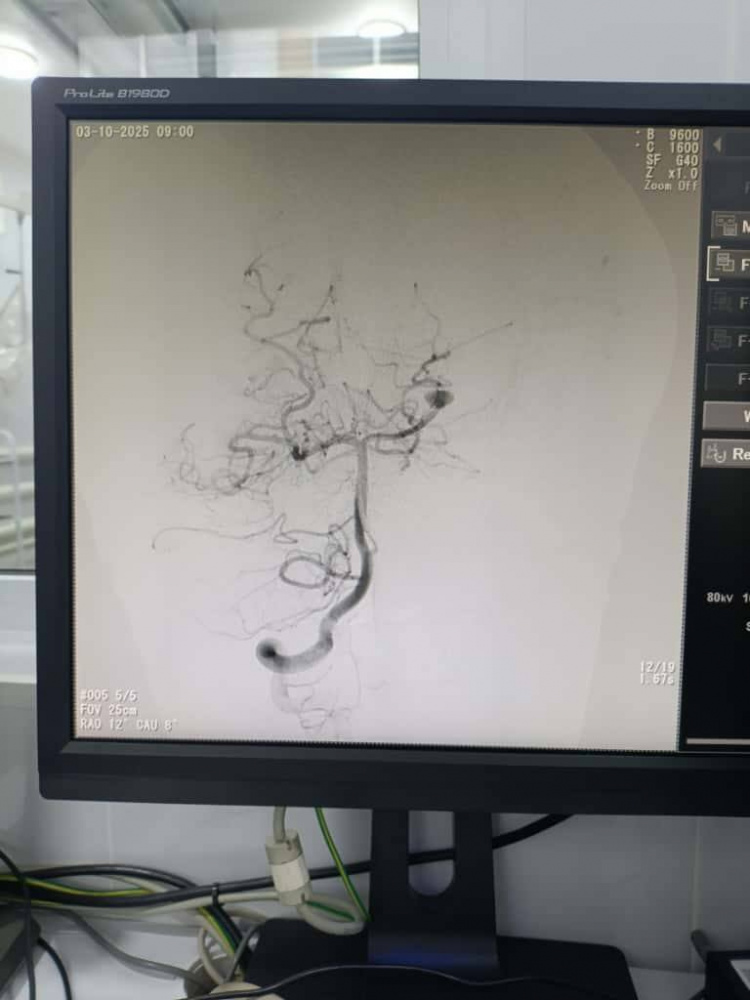

Нейрохирурги Национального центра охраны материнства и детства совместно с коллегами из Национального госпиталя провели высокотехнологичные эндоваскулярные операции у детей с тяжелыми сосудистыми патологиями головного мозга - аневризмами и артериовенозными мальформациями (АВМ). Информация об этом размещена в социальных сетях НЦОМиД.

Операции проводились в условиях современной ангиографической операционной с применением новейших методов интраоперационной визуализации.